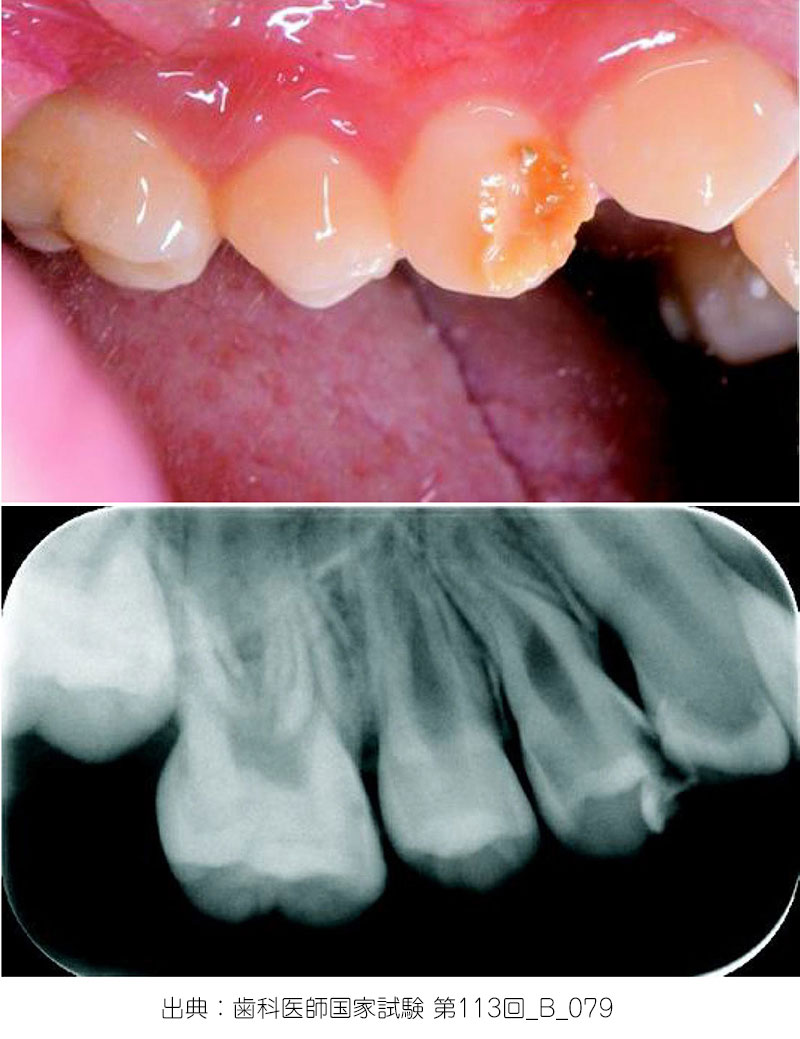

Turnerの歯

【原因】

・乳歯の慢性根尖性歯周炎

→後続永久歯に認められる

【特徴】

特に小臼歯部に多い